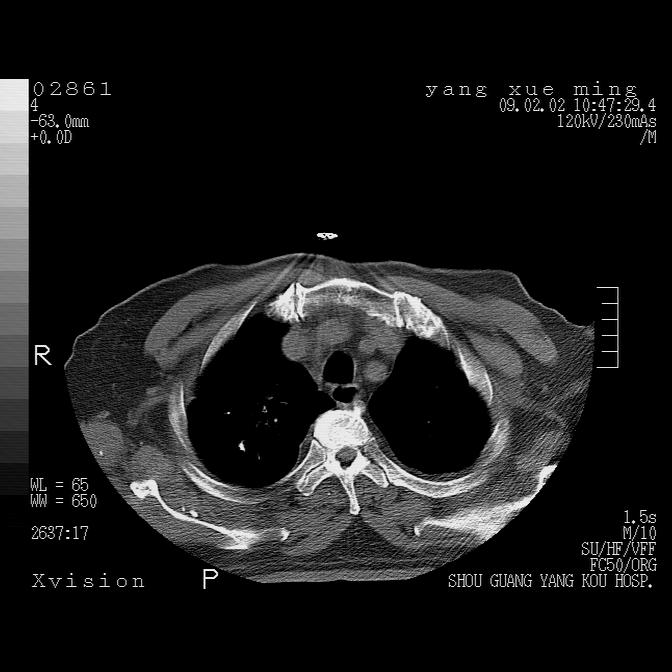

以下是引用zbp537在2009-2-3 19:08:00的发言:[br]我诊断为肺泡性肺水肿。[br]诊断依据:[br]1、心影普遍增大,肺血管增粗,并见絮状高密度影,肺门改变显著。[br]2、临床上表现胸闷咳嗽,无发烧,不是一个典型的肺部感染的病史。

以下是引用王仕学在2009-2-3 20:28:00的发言:[br]考虑右下肺感染,建议治疗后复查。

以下是引用lkc8963在2009-2-3 20:11:00的发言:[br]1)右上肺陈旧病灶。2)右下肺团块及团片影,影像表现符合感染。3)左心增大,左冠脉钙化,符合冠心病。4)双侧肺门扩大,以左侧为著,肺动脉干略粗,左上肺局限性气肿,为谨慎起见,需除肿瘤,建议增强。

以下是引用lkc8963在2009-2-3 20:11:00的发言:[br]1)右上肺陈旧病灶.2)右下肺团块及团片影,影像表现符合感染.3)左心增大,左冠脉钙化,符合冠心病.4)双侧肺门扩大以左侧为著,肺动脉干略粗,左上肺局限性气肿,为谨慎起见,需除肿瘤,建议增强.